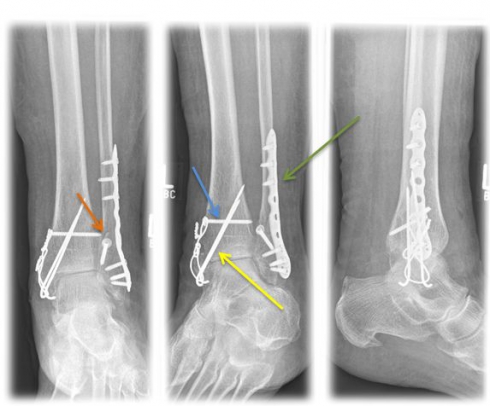

Method of choice in surgical therapy

- Internal ankle fracture: mostly use of cannulated screws or tension belt osteosynthesis

- Outer ankle fracture: usually insertion of a lag screw and a neutralization plate

- tape seam may be necessary if the inner tape can be folded out

- In case of syndesmosis injury, the insertion of an adjusting screw is necessary for 6 weeks to stabilize the syndesmosis.

Fig. 4) Osteosynthetic treatment of a bimallel ankle fracture by means of tension belt osteosynthesis at the inner ankle (yellow arrow), neutralization plate (green arrow) and a traction screw (orange arrow) at the outer ankle as well as an adjusting screw (blue arrow).